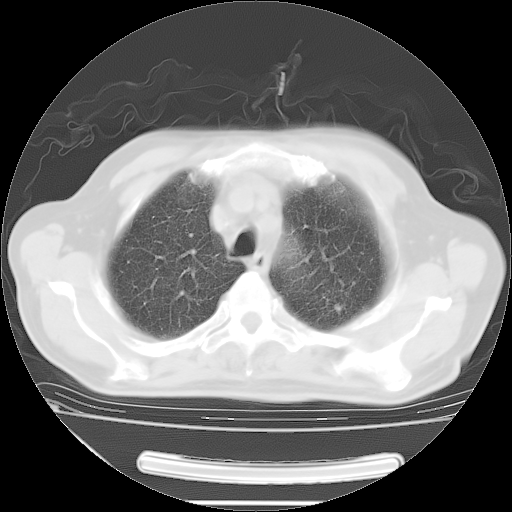

今天复查肺部CT,发现双肺广泛磨玻璃样改变。所以我把3月19日和5月9日相隔50天的肺部CT上传。请大家会诊。

2009年3月19日肺部CT片。

5月9日肺部CT(在4月27日齐鲁医院肺部CT描述部分肺组织磨玻璃样改变,12天后肺组织广泛磨玻璃样改变)

大致读了系列胸部CT:纵隔窗无明显异常,肺窗:从4、27至今:主要是双肺中下野外带可见毛玻璃样改变,目前处于急性肺泡炎阶段,至于原因考虑1、结替组织或胶原血管性疾病所致?2、恶性疾病如恶组在肺部所致的表现或细支气管肺泡癌?3、药物或其它原因如肺蛋白沉着症所致肺泡炎目前不太可能?总之,明天就去请我院的呼吸科、感染科、血液科和临免专家会诊哈。